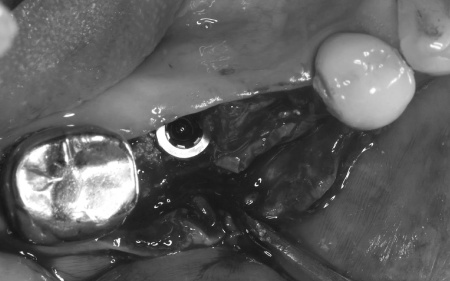

治療中

インプラント体と骨の結合を確認しました。